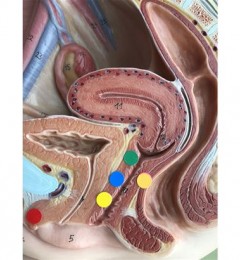

NIFTY是一种非侵入性的胎儿染色体检测技术。仅需抽取孕妇的静脉血,即可检测胎儿是否患有唐氏症等染色体疾病。与羊膜穿刺最大差异,在于它取的是母血(婴儿的游离染色体会透过胎盘进入母体血液),但羊膜穿刺取的是羊水(胎儿的完整染色体)。

这也是为什么NIFTY目前仍无法完全取代羊膜穿刺染色体检查。因为它能检测出的是染色体「数量」的异常,比方说唐氏症是21号染色体多一条,爱德华氏症是第18号染色体多一条等等,准确率高达99%,但就仅限于第13、18、21对染色体。但对于染色体结构的异常,并无法检验出来,所以国际间共识还是将NIFTY视为一种筛检技术,这也是为什么如果做了NIFTY结果为异常,会建议再做羊膜穿刺染来确认。